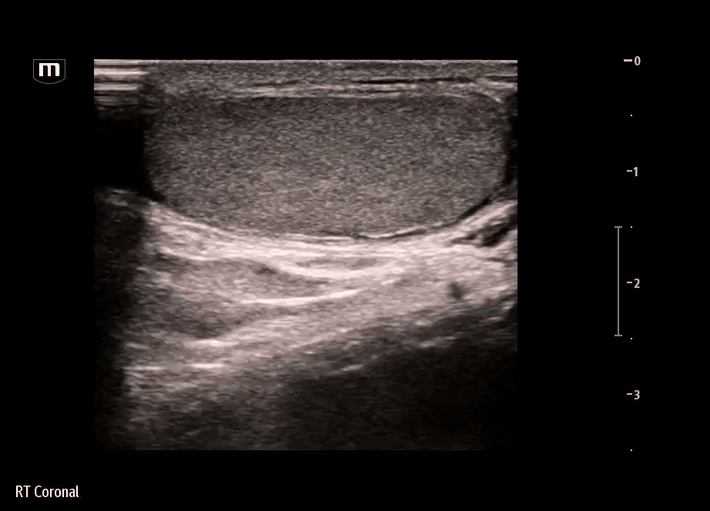

Ultrasound:

Ultrasound was performed on the R scrotum

Findings on our bedside ultrasound:

• The structure is anechoic - fluid-filled, appears to be simple fluid

• The structure has no peristalsis, and there is a lack of typical bowel wall findings - probably not bowel or inguinal hernia

• The structure does not seem to be within the tunica vaginalis - not a hydrocele, where the simple fluid collection would be seen surrounding the testicle itself